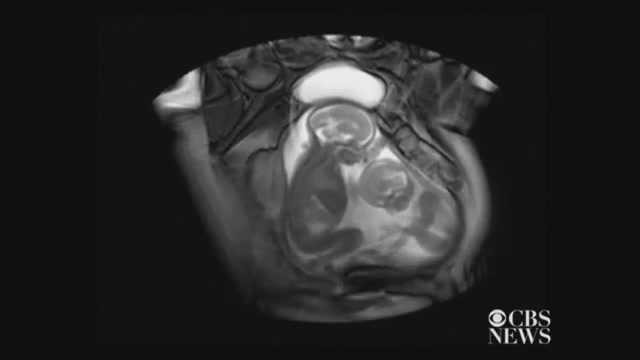

(VTC News) - Các nhà nghiên cứu tại London, Anh đã ghi lại được đoạn clip “đá nhau giành chỗ” rất thú vị của một cặp thai đôi qua hình ảnh siêu âm.

(VTC News) - Các nhà nghiên cứu tại London, Anh đã ghi lại được đoạn clip “đá nhau giành chỗ” rất thú vị của một cặp thai song sinh qua hình ảnh siêu âm.

Nguồn: CBS News